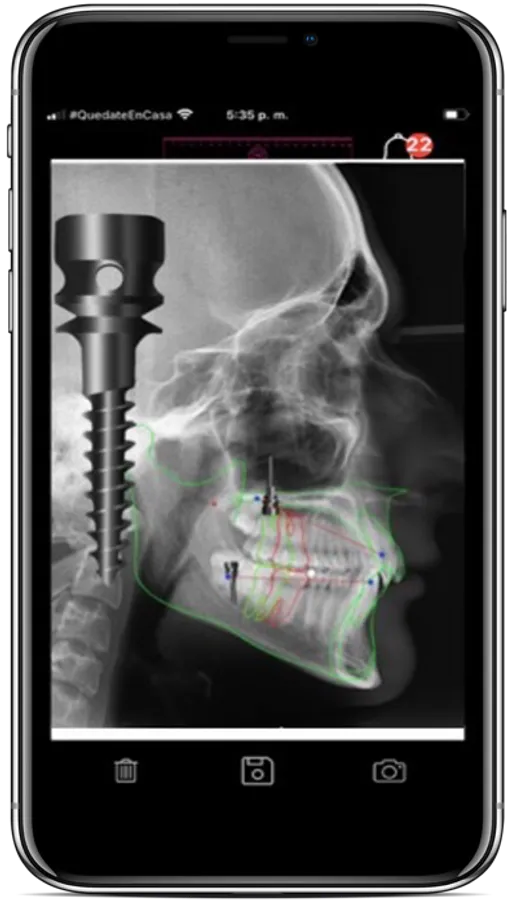

Funciones adicionales le permitirán realizar planeación de la biomecánica ortodóntica convencional y con mini-implantes, planeación de la restauración en implantología, lectura de la anatomía articular de la A.T.M y su relación con el plano oclusal, captura, almacenamiento y socialización de imágenes en redes entre otras.

d- Lectura de las posiciones dentales y predicción de movimiento dental

e- Lectura y programación del torque anterior